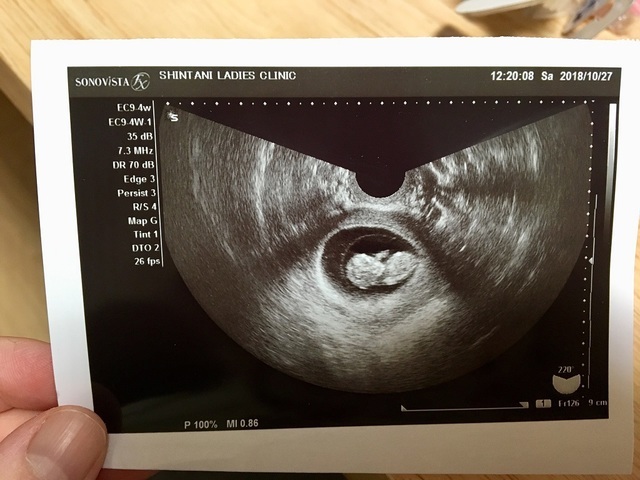

10週0日(10w0d・性別不明)|あずみん。 さん(30歳)

エコー写真撮影時のエピソード:

つわりがつらくて旦那がはじめて健診に付き添ってくれました、エコーで赤ちゃんを見て、ほんまに居るんやなぁと、しみじみ、まだ10週なのに、お医者さんが、ひと言、顎シャープですねー!…すでに旦那似でした。それからというもの、全ての健診に付き添ってくれています。私にも甘いのですが、子どもにも絶対優しいパパになる確信に繋がりました!何にも不安はありません。